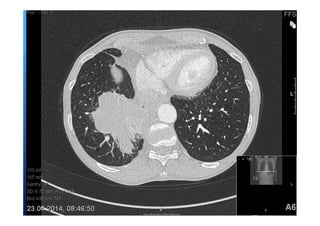

52 jährige Patientin

Gewichtsverlust

Adynamie

Nachtschweiß

Immer wieder Fieber über 12 Monate

Raucherin > 30 packyears

Lungensequester mit

infradiaphragmaler arterieller

Blutversorgung